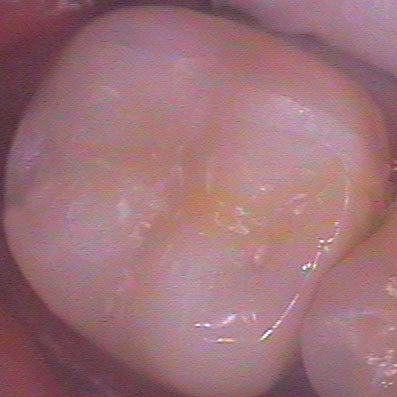

На снимката вляво - долен втори молар с циментирана композитна вставка (случай на

д-р Явор Симеонов). Вижда се запазена стена от зъба в горната част на

снимката. Възстановяването е заснето 20 месеца след поставяне върху

зъба, налице е отлична адаптация и пълна липса на вторичен кариес или

каквото и да било оцветяване по границите композит/твърди зъбни тъкани.

В случая не се наблюдава загуба на блясъка на композита - нещо, което не

винаги е налице, както посочихме по-горе. Какво бихме могли да кажем в

заключение? Композитната вставка е може би оптималното съотношение

цена/качество за възстановяване на зъб с голям кариозен дефект.

Същевременно за нейната изработка не се изисква отнемане на голямо

количество здрави зъбни тъкани, както е при обвивната корона.

Подготовката на зъба, снемането на отпечатък и циментирането на вече

готовата вставка отнемат по-малко клинично време в сравнение с

изработката на пломба; недостатък обаче е необходимостта от повторно

посещение в кабинета. Все пак сумарно двете посещения почти винаги като

време отнемат по-малко от времето за изработка на конвенционална пломба.

Това е от значение за пациенти, които не обичат да прекарват много време

на стоматологичния стол. Налице е и друго значително предимство на композитните пред

керамичните вставки - възможността за извършване на многократни корекции във

всяко едно отношение. При поява на пукнатини между вставката и зъба е възможно

да се извършват наслагвания на композитен материал; също така са възможни

корекции във формата и цвета на възстановяването, тъй като композитите за

клинично приложение са тотално съвместими и осигуряват химична връзка с

лабораторните композити. Това предимство следва да се има предвид при съзъбия с

повишена склонност към развитие на кариес - дори и след години при развитие на

кариозен дефект в съседен участък могат да се извършват наслагвания и репаратури

във всякакъв обем без цялостна подмяна на вставката.